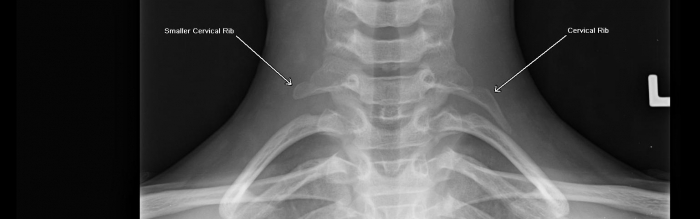

Шейные ребра с7

Шейные ребра с7 101 фотографий